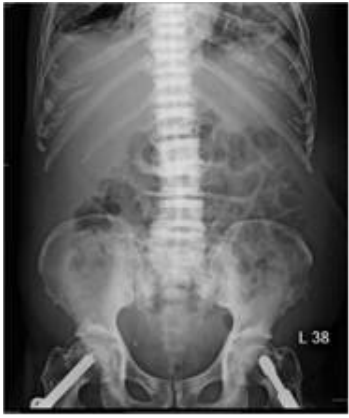

72.75歲男性,副甲狀腺素血液濃度上升,腹部X光檢查如附圖,其脊椎骨的變化為何? (A)renal osteodystrophy (B)ankylosing spondylitis (C)metastasis (D)osteomyelitis